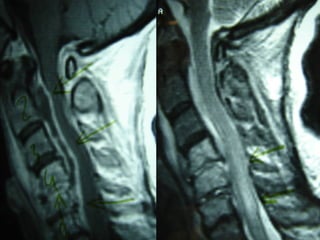

Spinal MRI is the procedure of choice

(sensitivity 95%, specificity 92%).

Gadolinium enhancement increases sensitivity

and enables better differentiation between

abscess and surrounding neurological

structures.

MRIMRI